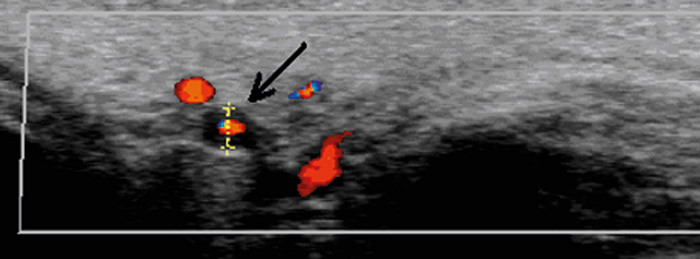

Pasienten ble innlagt i Nevrologisk avdeling med mistanke om sentralarterieokklusjon eller temporalisarteritt. Nevrologisk undersøkelse var upåfallende, med unntak av visustap venstre side. Pasienten hadde ikke hodepine. Temporalisarterien var verken hoven eller trykkøm, CRP var 19 mg/l (referanseverdi < 5 mg/l) og senkningsreaksjonen var 25 mm/t (referanseverdi < 30 mm/t). Ultralydundersøkelse av temporalarterien viste hypoekkoisk halo i arterieveggen som tegn på veggødem (bildet til høyre). Biopsi viste kjempeceller samt inflammatoriske forandringer i og rundt arterieveggen (bilde kun i Tidsskriftets nettutgave) og bekreftet diagnosen temporalisarteritt.

Pasienten ble behandlet med prednisolon. CRP sank til 3,3 mg/l og senkningsreaksjonen til 10 mm/t. Smertene forsvant, og synet på høyre side kunne bevares. Nytteverdien av ultralydundersøkelse ved spørsmål om temporalisarteritt er omdiskutert, men den var nyttig i dette tilfellet, da det var uvanlige kliniske tegn med lav CRP, lav senkning samt fravær av hodepine.